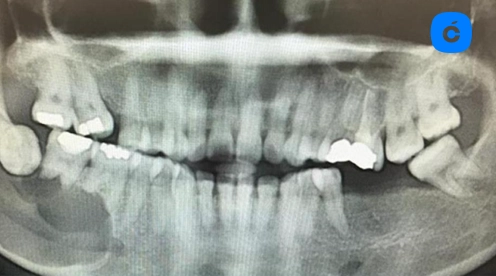

Radiografía periapical: Esencial para visualizar el área periapical. En abscesos periapicales agudos iniciales puede no observarse cambios radiográficos significativos. En etapas más avanzadas se aprecia radiolucidez periapical indicativa de reabsorción ósea.

Radiografía panorámica: Útil para evaluación de extensión, afectación de estructuras anatómicas y presencia de múltiples focos infecciosos.